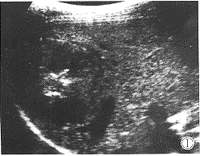

例2,男,39岁,因右上腹闷痛不适1个月入院,无伴畏寒发热,入院后检查HBsAg阴性,肝功能与血AFP检测值正常。CT检查示右肝占位性病变,大小为5.2cm×5.6cm,边缘清晰,内可见小点状高密度灶分布,增强后病灶迅速由周边向内强化,延时后病灶基本呈等密度状态。B超检查显示右肝一稍低回声团块,大小为5.2cm×5.7cm,境界尚清晰,内回声不均,中央可见众多强回声粗光点聚集,后方见弱声影(图1),B超考虑右肝占位性病变(肝脓疡后期?,恶性肿瘤?)。术中见右肝内一圆形肿物6cm×5cm×5cm,境界清晰,质地韧,包膜光滑完整,病理报告为右肝纤维瘤。

图1 右肝纤维瘤:境界清晰,回声不均,中央见众多点状强回声聚集,后方见弱声影。